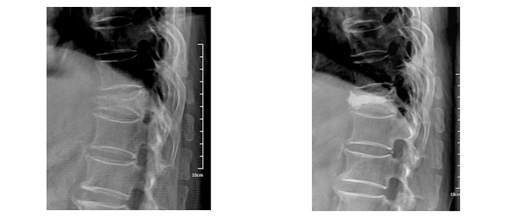

°æÇÇÀû ôÃßü ¼ºÇü¼ú

¼ö»ó ÈÄ ¾à 2ÁÖ°£ ħ»ó ¾ÈÁ¤°¡·á, Àû±ØÀû º¸Á¸Àû Ä¡·á ÈÄ¿¡µµ ÅëÁõÀÌ È£ÀüµÇÁö ¾Ê°í ôÃß»À°¡ °è¼Ó ÁÖÀú¾ÉÀ¸¸é, ±¹¼Ò ¸¶ÃëÇÏ¿¡ ÁÖÀú¾ÉÀº ôÃß»À¿¡ ±½Àº ¹Ù´ÃÀ» »ðÀÔÇÏ¿© °ñÀýºÎÀ§¿¡ ¹Ð°¡·ç ¹ÝÁ× °°Àº '°ñ ½Ã¸àÆ®'¸¦ ÁÖÀÔÇÏ¿© ¼öºÐ ÈÄ ´Ü´ÜÈ÷ ±»°Ô ¸¸µé¾î °ñÀýºÎÀ§¸¦ °íÁ¤ÇÏ¿© ÅëÁõ ¼Ò½Ç°ú Ãß°¡ ¾Ð¹ÚÀ» ¹æÁöÇϰíÀÚ ÇÏ´Â ½Ã¼úÀ̸ç, ½Ã¼ú½Ã°£Àº ¾à 20ºÐ Á¤µµ ¼Ò¿äµÇ¸ç °ñ´Ù°øÁõÀÌ ÀÖ´Â °æ¿ì¿¡´Â °ÅÀÇ ÅëÁõÀÌ ¾ø½À´Ï´Ù.